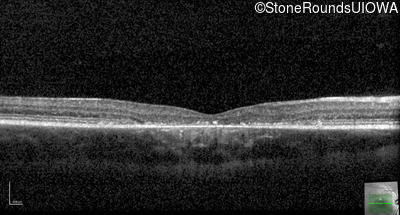

Optical Coherence Tomography - Right - 20/80 -1

Exemplar / OCT Stack